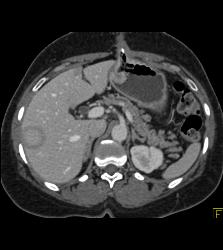

Tumor Recurrence Along G-tube With Liver Metastases